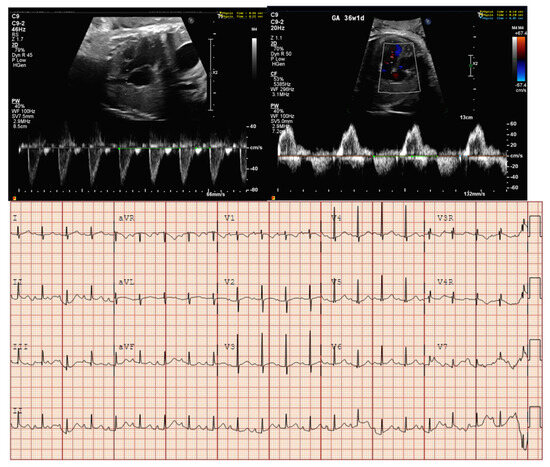

- Long VA SVT (Figure 4) demonstrates a VA interval that is more than half of the VV interval (VA:AV ratio > 1). Long VA SVT includes EAT and PJRT. A distinguishing feature of EAT is tachycardia termination with ventricular contraction. Long VA SVT may occur as early as 12 weeks of gestation. Because long VA tachycardias have slower rates, they are less likely to cause hydrops.